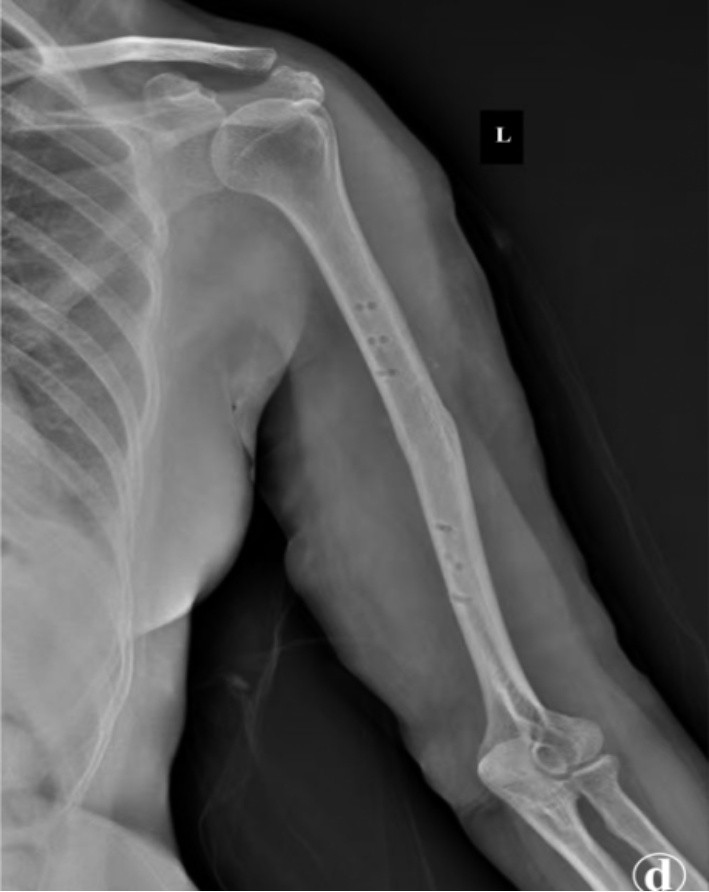

患者术后恢复顺利,无桡神经麻痹、切口感染、血管损伤等并发症。术后1天复查X线片示骨折解剖复位,内固定位置良好(图2)。术后第2天开始进行肩、肘关节被动功能锻炼,逐步过渡至主动活动。术后6个月随访X线片显示骨折线模糊,骨痂形成良好,内固定无松动、断裂(图3)。术后16个月返院拆除内固定装置,X线片示骨折愈合牢固,无畸形(图4)。拆除内固定前,手术切口愈合良好,瘢痕隐蔽,患者对外观满意(图5)。截至末次随访,患者肩关节平均主动前屈达165˚ ± 10˚,外展155˚ ± 12˚,内旋达到T8椎体水平;肘关节平均主动活动范围(屈–伸)为125˚ ± 15˚(屈曲140˚ ± 5˚,伸直15˚ ± 10˚),前臂平均旋前80˚ ± 5˚,旋后85˚ ± 5˚。采用标准化量表评估,患者平均DASH上肢功能障碍评分为12分 ± 5分,表明仅有轻度功能障碍;平均MEPS肘关节功能评分为92分 ± 6分,对应“优秀”等级。疼痛控制方面,术后平均静息态VAS疼痛评分为1.5分 ± 1.0分,活动时为2.5分 ± 1.5分,已恢复正常工作和生活。

Figure 4. Radiograph obtained 16 months postoperatively, following removal of the internal fixation device

4. 术后16个月拆除内固定装置后